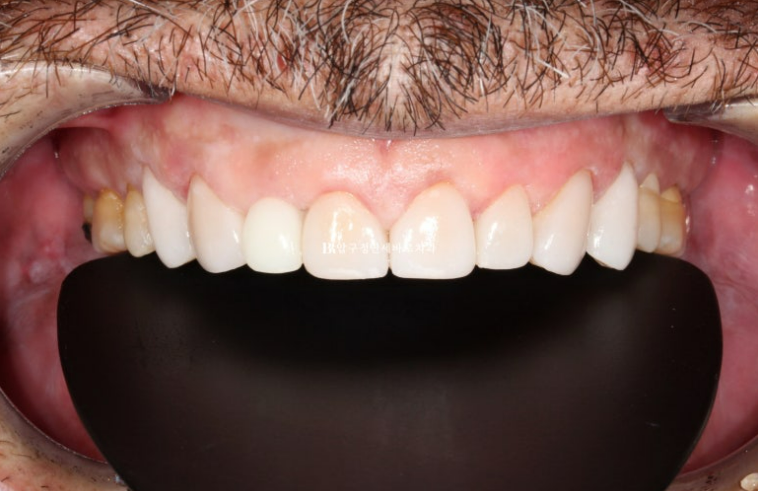

3개월에 걸쳐 앞니 교정을 간단하게 하고 6월 드디어 무삭제 라미네이트 치료를 했습니다.

24.06

중년 부분교정 후기

옥니 치아가 교정과 무삭제라미네이트로 개선이 되었습니다.

미소가 훨씬 젊어보입니다.